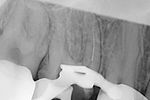

Revisionsbehandlung eines Unterkiefermolaren (37) vor geplanter Überkronung (Dr. Maik Göbbels) Download